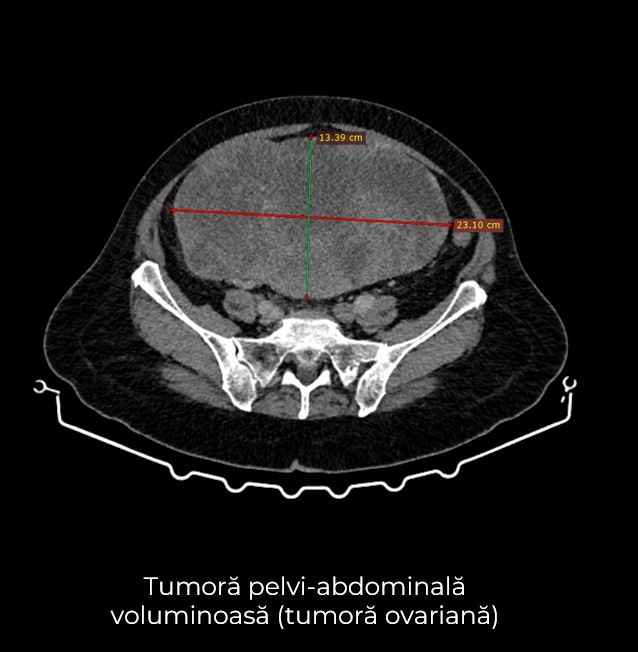

Uneori, o durere aparent banală ascunde în spate o realitate medicală mult mai serioasă. Așa s-a întâmplat și în cazul unei paciente de 63 de ani, care a ajuns la spital pentru dureri pelvine persistente. Investigația CT a schimbat însă complet perspectiva: au fost descoperite trei formațiuni tumorale în zone diferite ale corpului – o tumoră mamară stângă (carcinom mamar invaziv biopsiat), o tumoră pelvi-abdominală voluminoasă (tumoră ovariană) și o formațiune la nivelul peretelui posterior gastric (leiomiom gastric biopsiat).

- Histerectomie totală cu anexectomie bilaterală – îndepărtarea uterului și a ovarelor, cu verificarea histopatologică intraoperatorie a tumorii ovariene ce a relevat carcinom ovarian, limfadenectomie pelvină și interaortico-cava, omentectomie, biopsii peritoneale multiple.